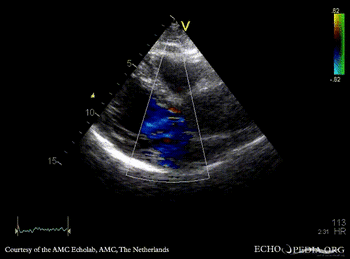

30 Aortic dissection

E00245.gif

Subcostal view: dissection flap in abdominal aorta